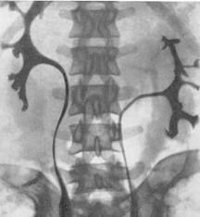

Торакальная дистопия почки диагностируется при проведении профилактической флюорографии или обзорной рентгенографии грудной клетки. Дистопированная почка чаще определяется как плотная округлая тень в заднем средостении над диафрагмой. Для правильной диагностики дистопии почки и ее формы применяются визуализирующие урологические методы - УЗИ почек, ретроградная и экскреторная урография, радиоизотопная ренография (сцинтиграфия), почечная ангиография, МРТ, МСКТ почек.

УЗИ почек позволяет определить отсутствие почки на своем анатомическом месте и дифференцировать дистопию с нефроптозом. Экскреторная урография, как правило, точно выявляет аномальную локализацию почки, степень ее ротации и ограниченную подвижность. При резком снижении функции почек выполняется ретроградная пиелография. В ходе почечной ангиографии устанавливается уровень отхождения почечных артерий от ствола аорты.